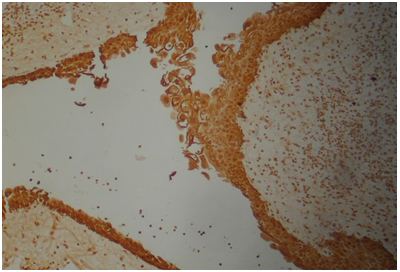

HMW cytokeratin was positive in all 22cases in all squamous parts (Figure 4). Cytokeratin 19 was positive in PBC and SR but negative in SMS and WK parts (Figure 5). Cytokeratin 20 was negative in all squamous parts. LMW cytokeratin: was positive in the PBCs and SMS but reduced in SR and negative in WK in 17/22cases (Figure 6). Cytokeratin 7 was positive in the SR but not in the PBC, SMS or WK in 19/22cases (Figure 7). Cytokeraitn 5/6 was positive in all three layers SMS, SR and PBC but negative in wet keratin in 22/22 cases (Figure 8).EMA was positive in SR and WK, but negative in PBC and SMS in 17/22cases (Figure 9).p63 was positive in PBC and SR cells, but negative in WK and SMS in 16/22cases (Figure 10).p16 was positive in PBC and SR in 15/22cases (Figure 11).Twelve cases show positive p53 immunostainings with range 2%-50% of the cells (Figure 12). Ki67 showed more than 10% positivity in 13cases (Figure 13) and low positivity or negative in 12cases. B-catenin was positive in PBC in 11cases in cytoplasmic and nuclear pattern and was positive in 11cases in cytoplasmic pattern only.

Figure 4 HMWC was positive in all 22 cases in all squamous parts.